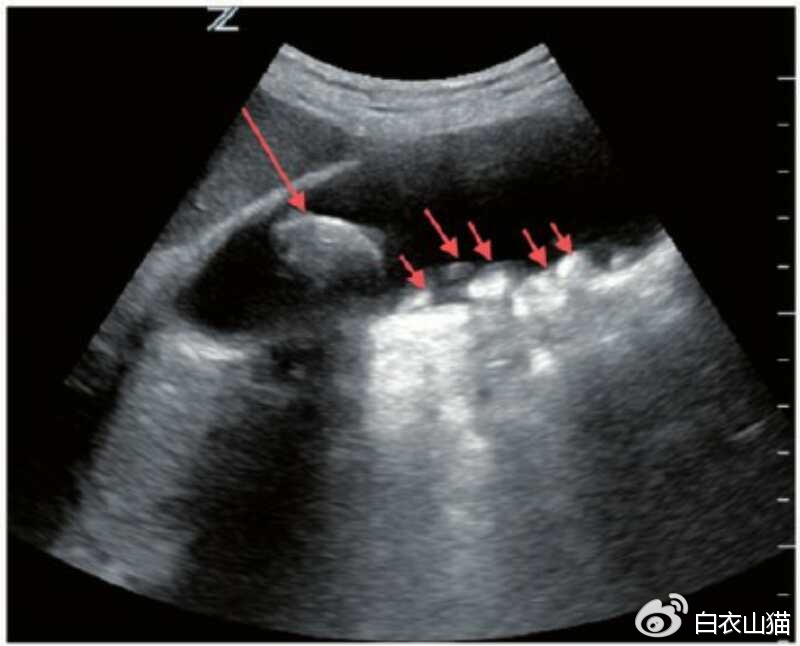

结石的B超表现有:胆囊腔强回声、后 方伴会有声影、声像具体表现会随着患者体位的改变 而发生移动现象。

红箭头指向结石。

息肉的B超表现有: 胆囊壁有强或稍强回声光团,其后无声影, 声像具体表现不会随着患者体位的改变 而发生移动现象。

部分结石,比如胆固醇结石,比较疏松的时候,可以没有声影。这个时候,恰好结石又粘附在胆囊壁上,当然不会随体位变化而移动啦。这部分结石,会被B超下判断为息肉。